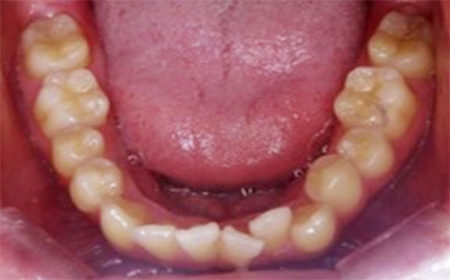

CASE08

Before

After

| 施術名 |

インビザラインコンプリヘンシブを用いた矯正治療(叢生) |

| 治療期間 |

1年 |

| 治療費 |

880,000円(税込) |

| リスク |

マウスピース装置により疼痛・咬合時痛を生じる事があります。割れたり壊れたりする事があります。 |

歯科医師からのコメント

「上顎八重歯が気になる」で来院されました。分析すると、軽度なねじれでしたのでインビザラインGoにて治療をすすめていきました。マウスピースを積極的に使用し、順調に治療がすすんでいきました。仕上がりにとても満足しておられました。